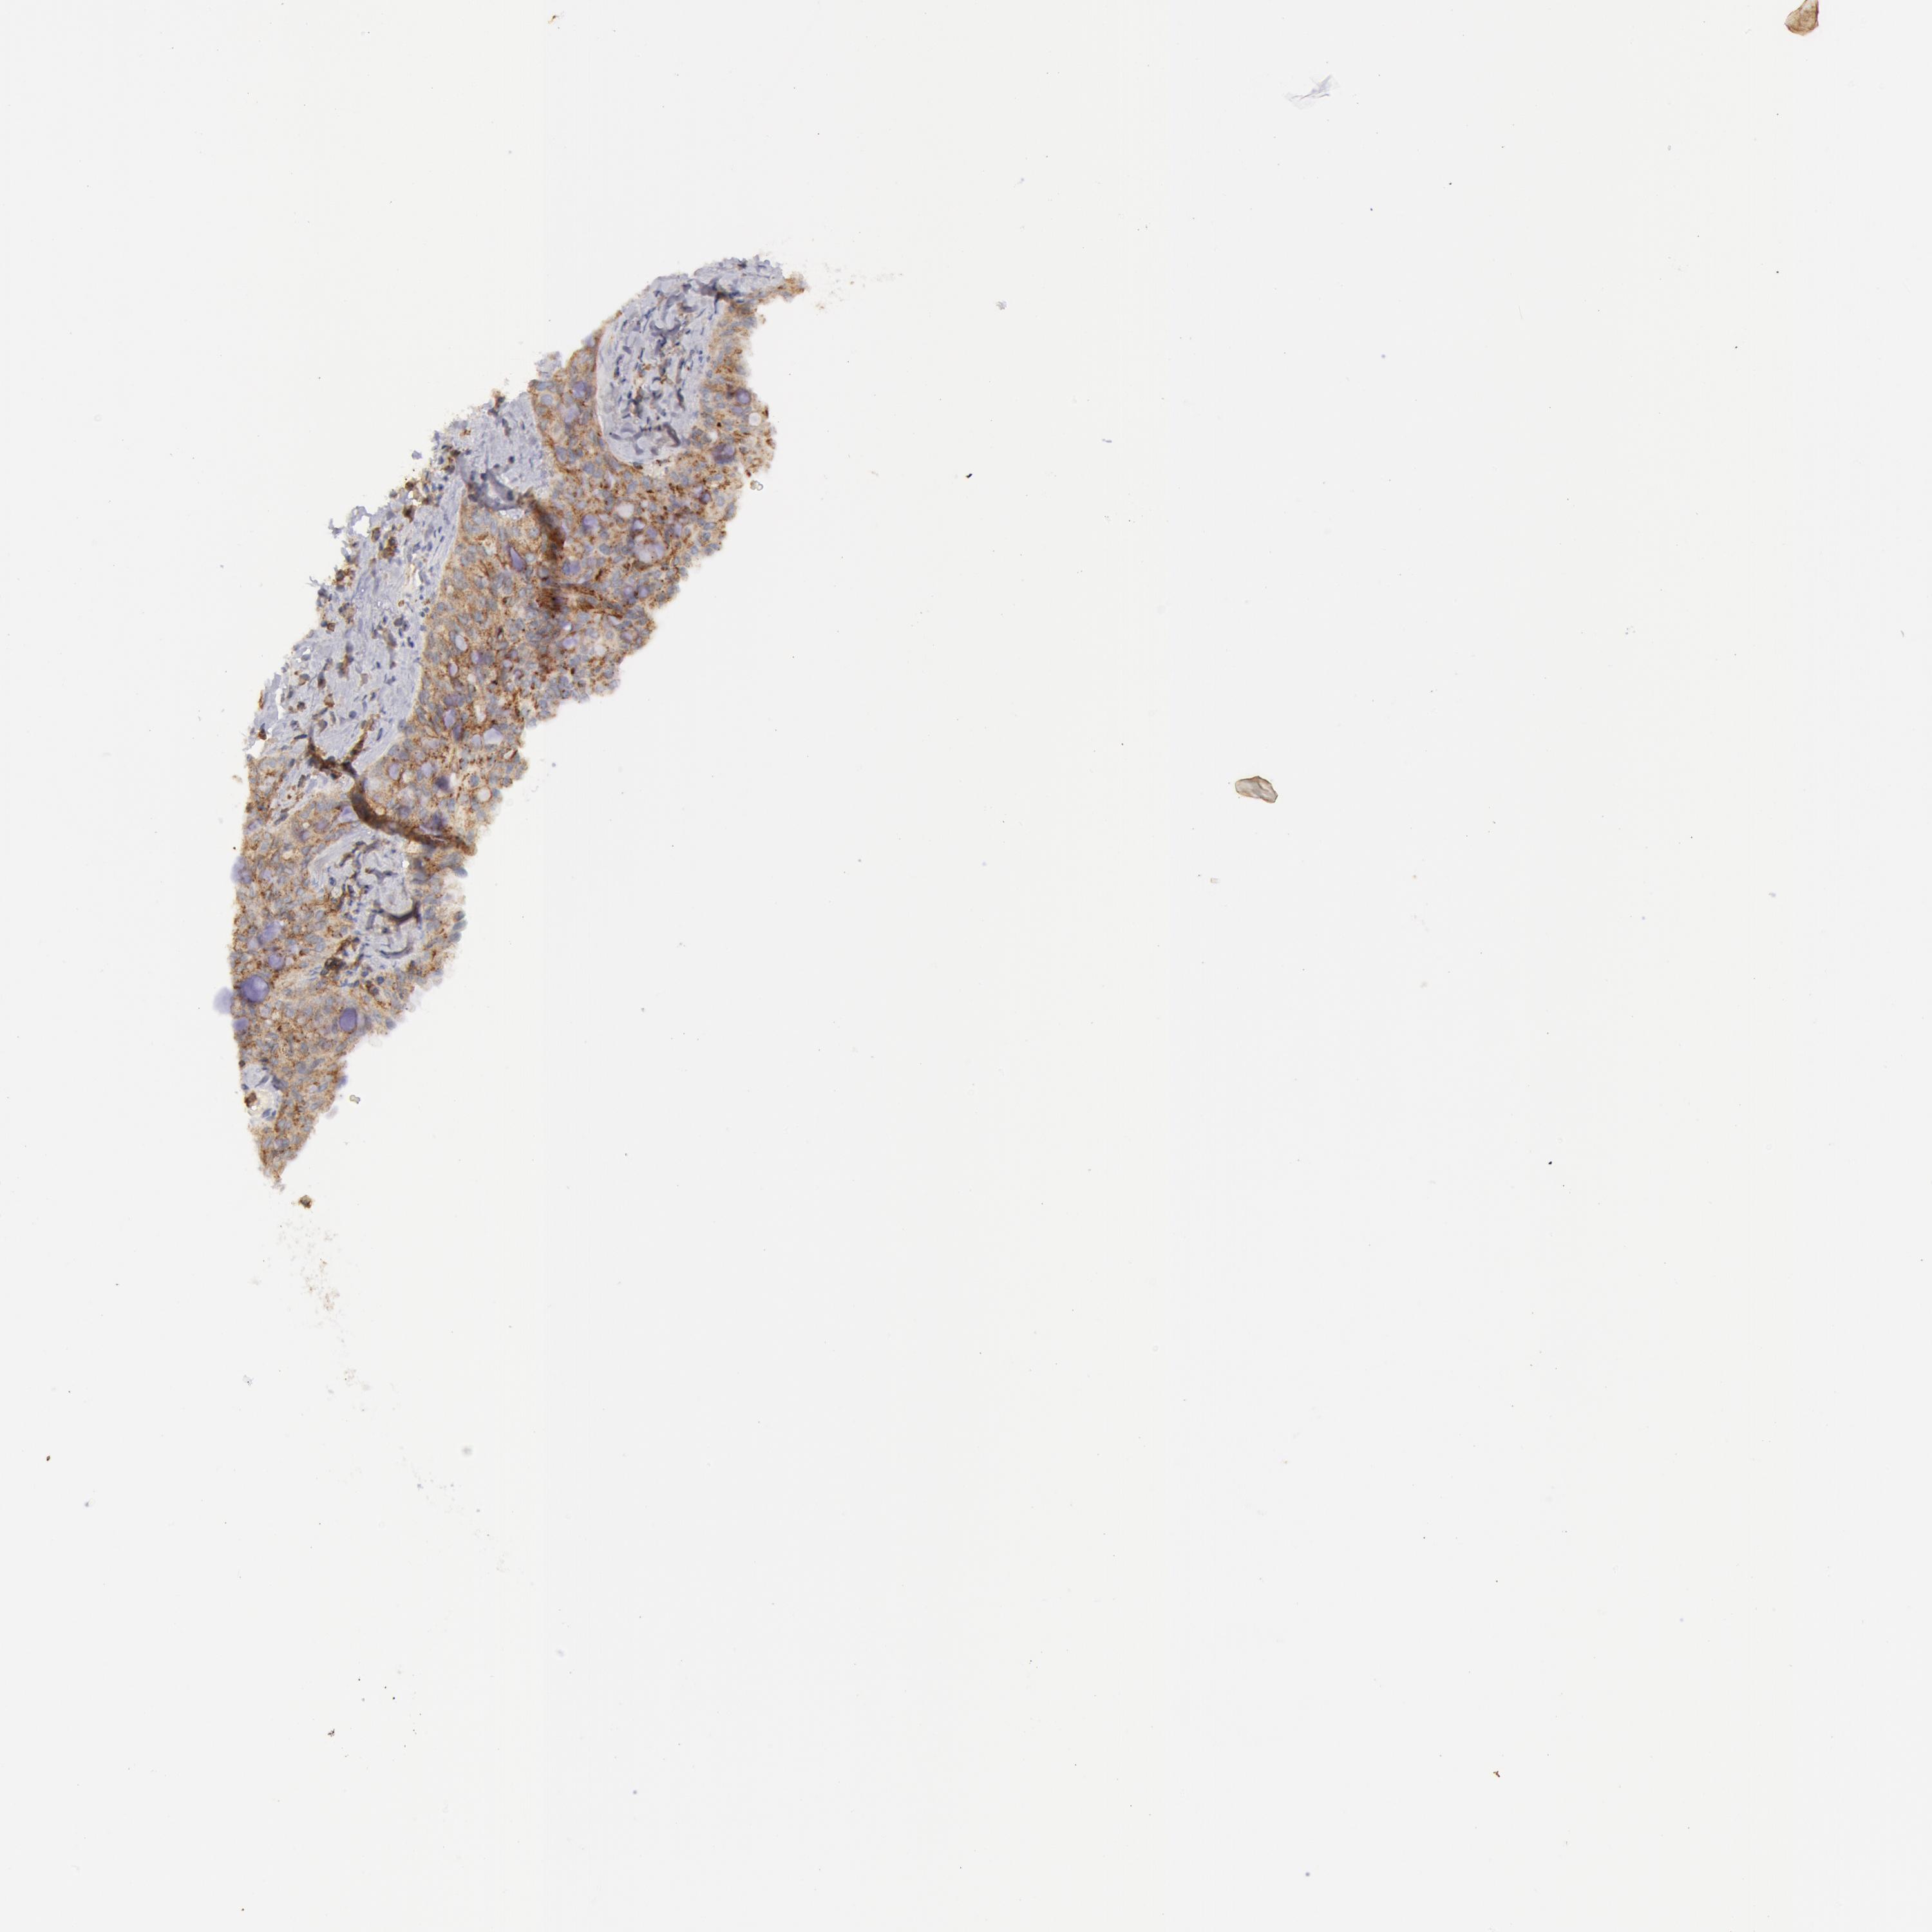

CANCER LUNG CANCER Show tissue menu

LUAD TCGA LUAD VALIDATION LUSC TCGA LUSC VALIDATION PROTEIN LUAD CPTAC PROTEIN LUSC CPTAC PROTEIN EXPRESSION

LUNG ADENOCARCINOMA (VALIDATION) - Interactive survival scatter ploti

FLOT2 is not prognostic in Lung Adenocarcinoma (validation)

: 50.56

: N/A

N/A

Average pTPM 51.2

Number of samples 105